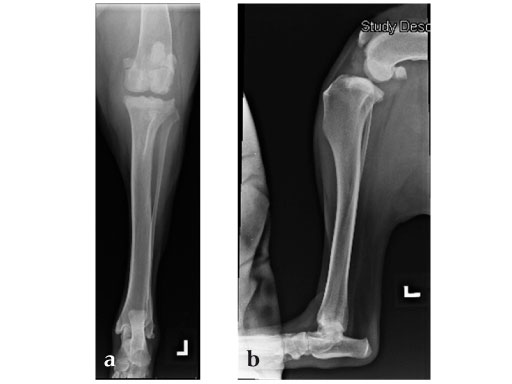

Case 1: Two-year-old Labrador Retriever

2-years-old Labrador Retriever, 30 kg, female. Chronic lameness in both hind limbs, chronic bilateral cranial cruciate ligament tears, with subsequent stifle joint instability and degenerative joint disease. At that time, she was more clinically lame on the left hind limb, and a surgical correction was subsequently performed on this limb. X-rays of the stifle joint revealed the degenerative joint changes and an effusion; the tibial plateau slope was 20. In addition, the x-rays confirmed that there was a slight amount of tibial torsion that also was observed clinically, accounting for a slight internal rotation of the distal limb. Radiographically, this could be assessed by a 4 mm shift of the normal point of intersection of the medial aspect of the calcaneus with the deepest point of the talar sulcus.

The stifle joint was surgically explored. All remaining remnants of the torn cranial cruciate ligament were debrided; in addition, the caudal pole of the medial meniscus was torn/crushed, and a partial meniscectomy of the damaged portion was performed. A TPLO plate 3.5 was applied to stabilize the fracture. The plate was applied in a neutral fashion. Postoperative x-rays revealed a tibial plateau angle of 5, and a correction of the torsion to 0 mm.

Follow-up x-rays at 8 weeks postoperatively revealed that the osteotomy had healed, and the dog was doing very well. The identical procedure was performed on the opposite stifle joint 2 months later. Healing was again obtained 8 weeks postoperative. Presently, the dog is about 1 year postoperatively and functioning very well.